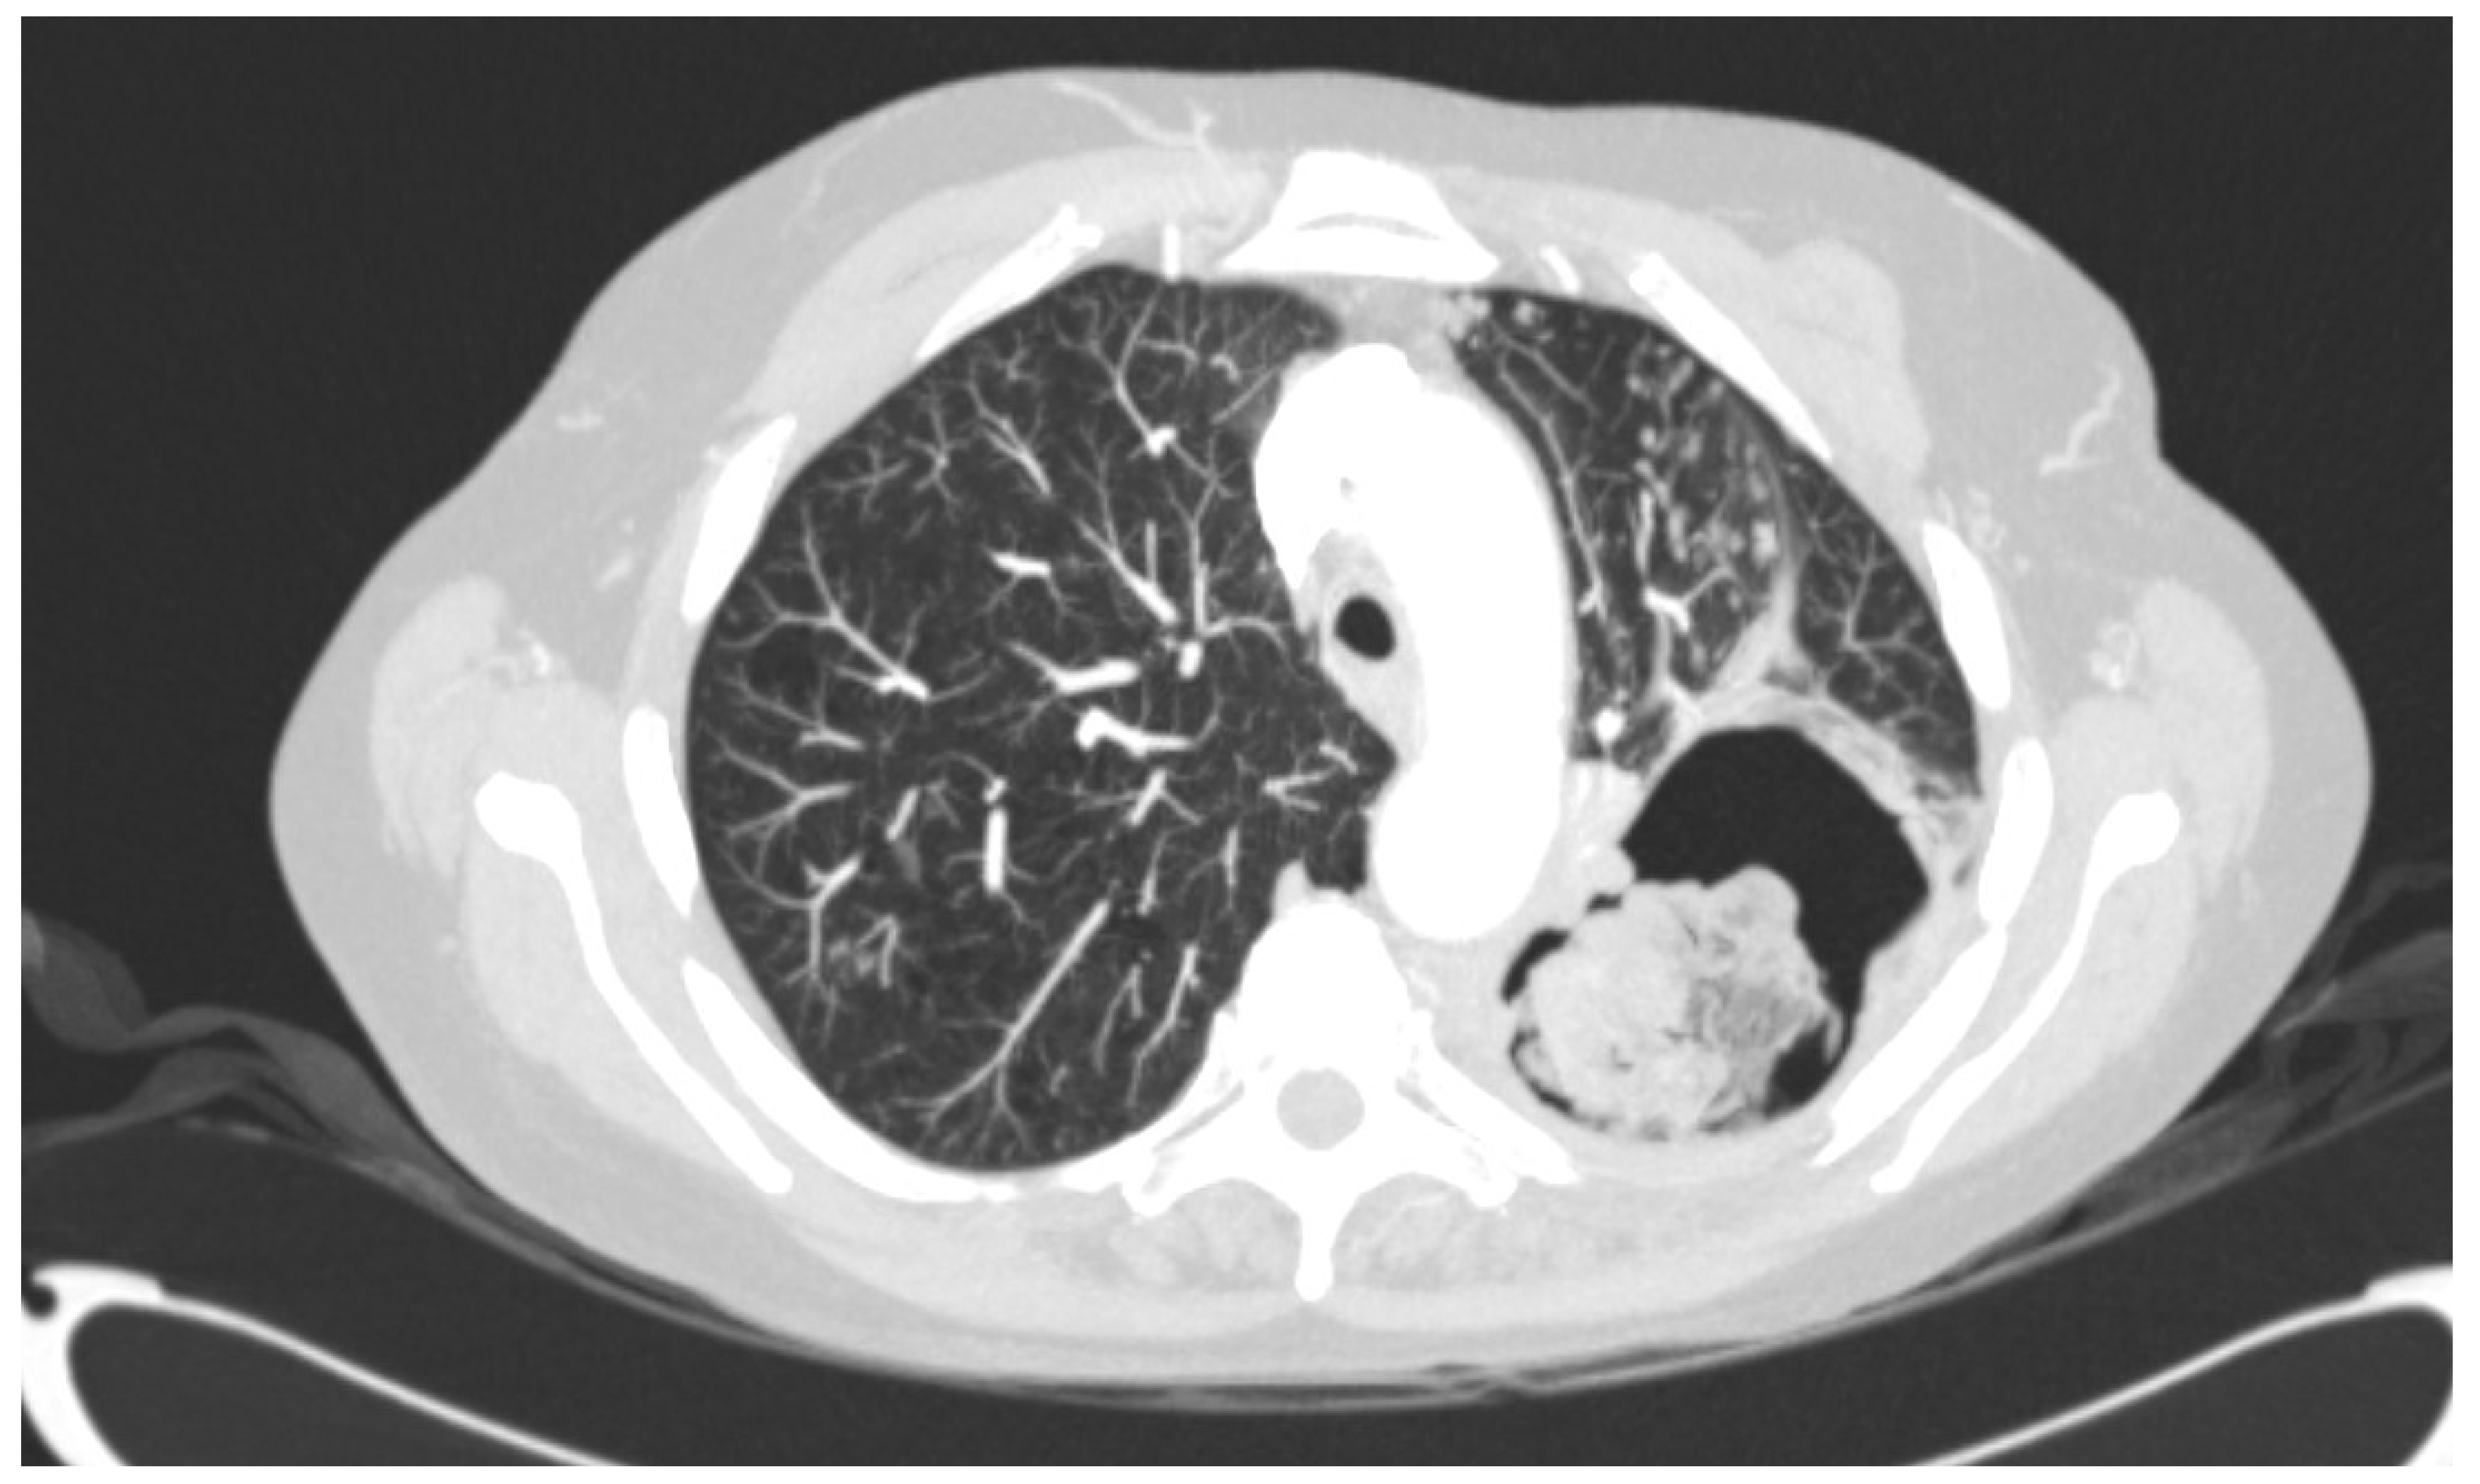

- Denning, D.W.; Cadranel, J.; Beigelman-Aubry, C.; Ader, F.; Chakrabarti, A.; Blot, S.; Ullmann, A.J.; Dimopoulos, G.; Lange, C.; European Society of Clinical Microbiology; et al. Chronic pulmonary aspergillosis: Rationale and clinical guidelines for diagnosis and management. Eur. Respir. J. 2016, 47, 45–68. [Google Scholar] [CrossRef] [PubMed]

- Smith, N.L.; Denning, D.W. Underlying conditions in chronic pulmonary aspergillosis including simple aspergilloma. Eur. Respir. J. 2011, 37, 865–872. [Google Scholar] [CrossRef] [PubMed]

- Juan Aguilar-Company; Martin, M.T.; Goterris-Bonet, L.; Martinez-Marti, A.; Sampol, J.; Roldan, E.; Almirante, B.; Ruiz-Camps, I. Chronic pulmonary aspergillosis in a tertiary care centre in Spain: A retrospective, observational study. Mycoses 2019, 62, 765–772. [Google Scholar] [CrossRef]